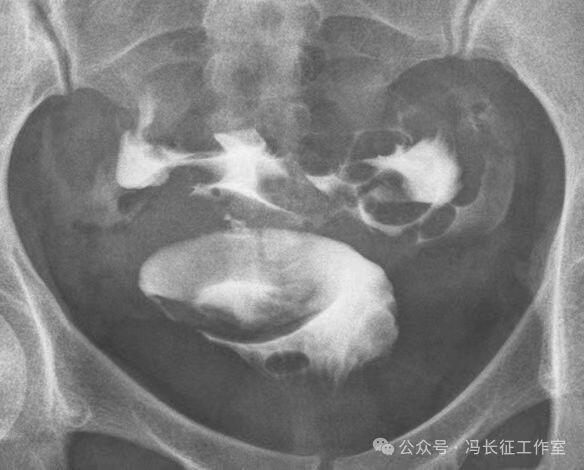

下面是一例正常子宫输卵管造影图(4张片)

微信图片_20240215160254.jpg